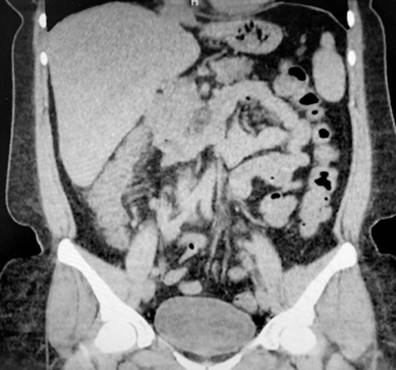

A 43-year-old female patient with a medical history of ankylosing spondylitis (AS) since the age of 20, fibromyalgia, arterial hypertension, hypothyroidism, and latent tuberculosis treated in 2019 presented to the hospital with symptoms of diffuse abdominal pain and multiple bloody diarrheal stools (more than fifteen times a day) for a week. The patient had been treated with etanercept, adalimumab, abatacept, and since 2017, with secukinumab. On admission, the patient was tachycardic, dehydrated, afebrile, and had lower abdominal pain without signs of peritoneal irritation. Laboratory tests showed no alterations in blood count, and an ultrasound and tomographic study revealed wall thickening of the right colon with mucous enhancement, multiple mesenteric lymphadenopathies, and some free fluid at the bottom of the sac (Figure 1). Colonoscopy showed edema, erythema, mucosal friability, loss of vascular pattern, and ulcerations covered by fibrin from the rectum to the cecum, which are consistent with extensive ulcerative colitis (Figure 2 ).